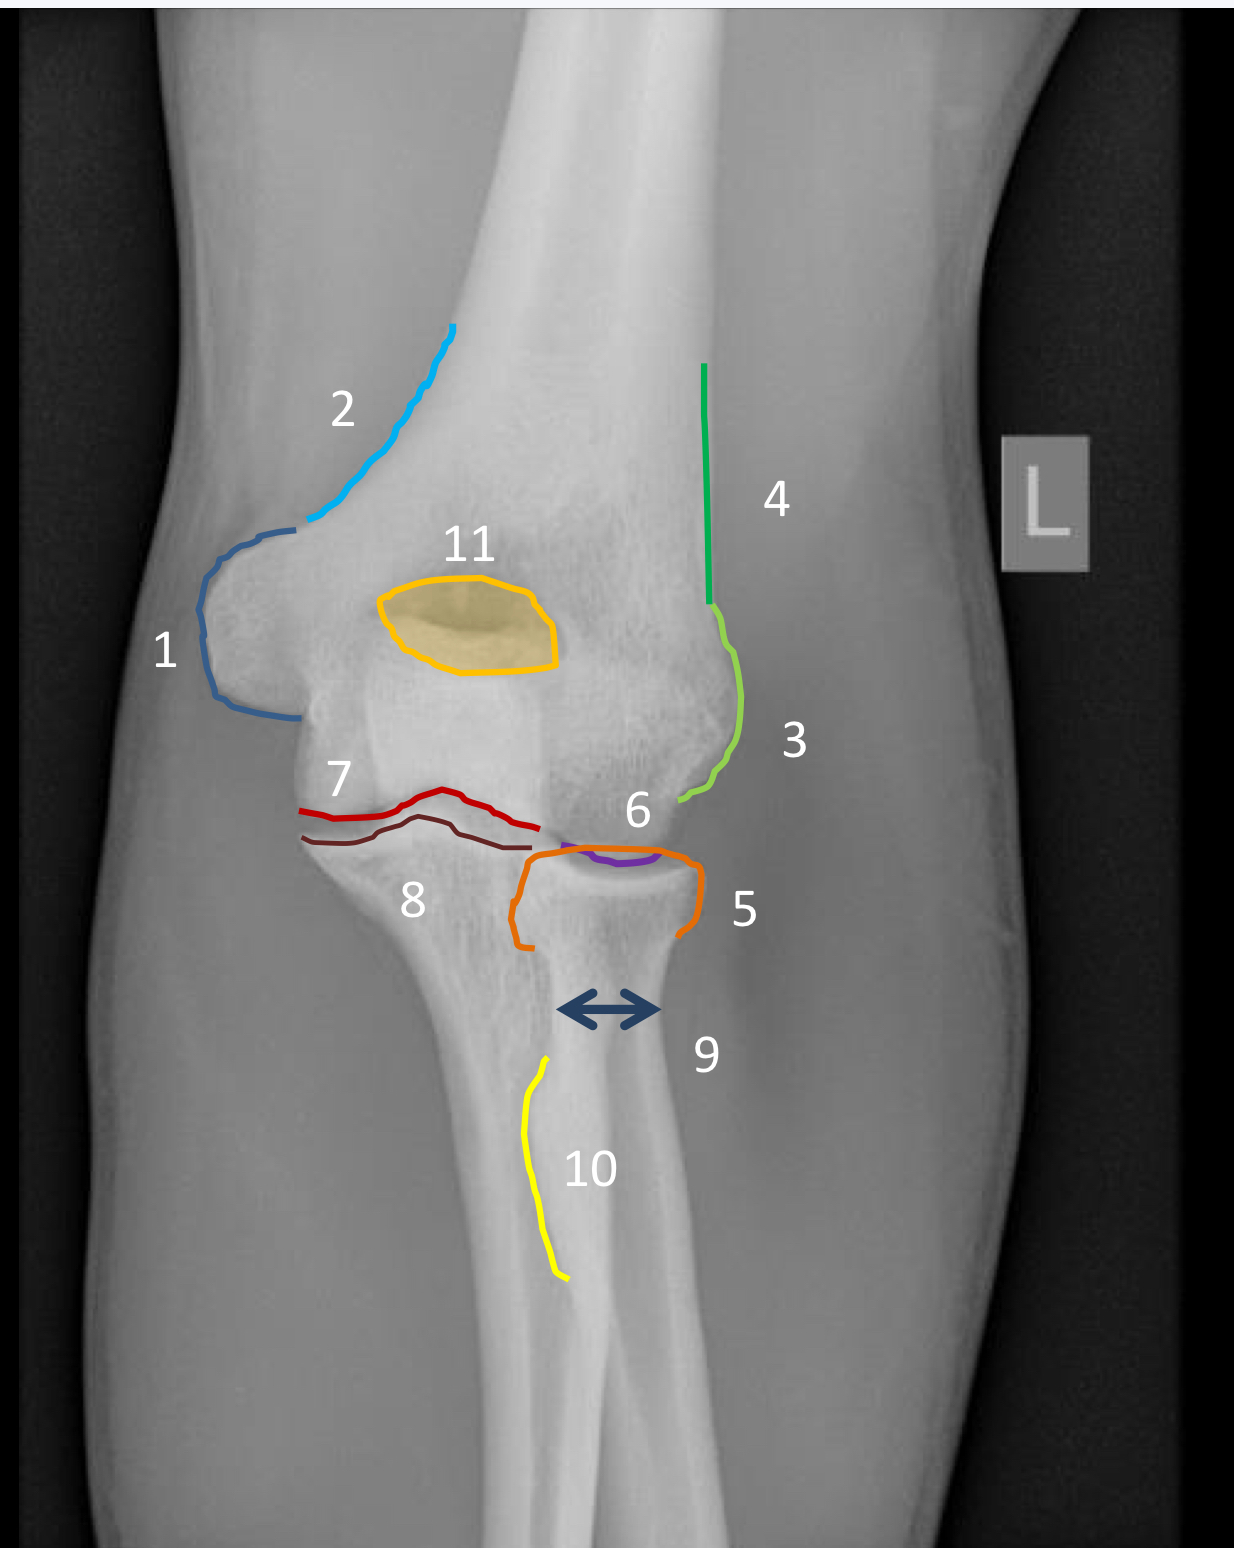

1?

olecranon fossa

2?

coronoid fossa

3?

olecranon process

4?

ulnar tuberosity

5?

capitellum

6?

trochlea

7?

trochlear notch

8?